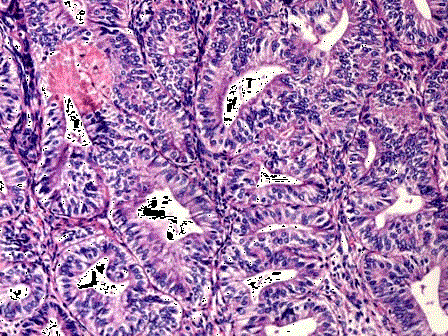

问题 女性,46岁,阴道不规则出血1年,诊刮子宫内膜,显微镜下见腺体增生密集,与间质比>3:1,腺体呈乳头状,可见背靠背现象,伴嗜酸性粒细胞浸润,腺上皮异型性并见核仁(如图),应诊断为 ( )

选项 A.子宫内膜单纯性增生 B.子宫内膜复杂性增生 C.子宫内膜单纯性增生伴非典型增生 D.子宫内膜复杂性增生伴非典型增生 E.子宫内膜腺癌